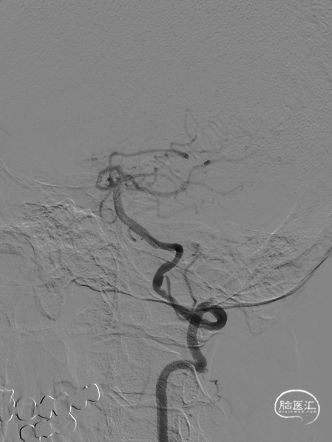

➢ 一期单纯球囊扩张成形术

长SIM与6F导引导管同轴,泥鳅导丝引导下将6F导引导管送至颈总动脉远端。

保护伞到位后释放(左图箭头),2.5*20mm通桥白驹®球囊以6atm扩张(右图箭头)。